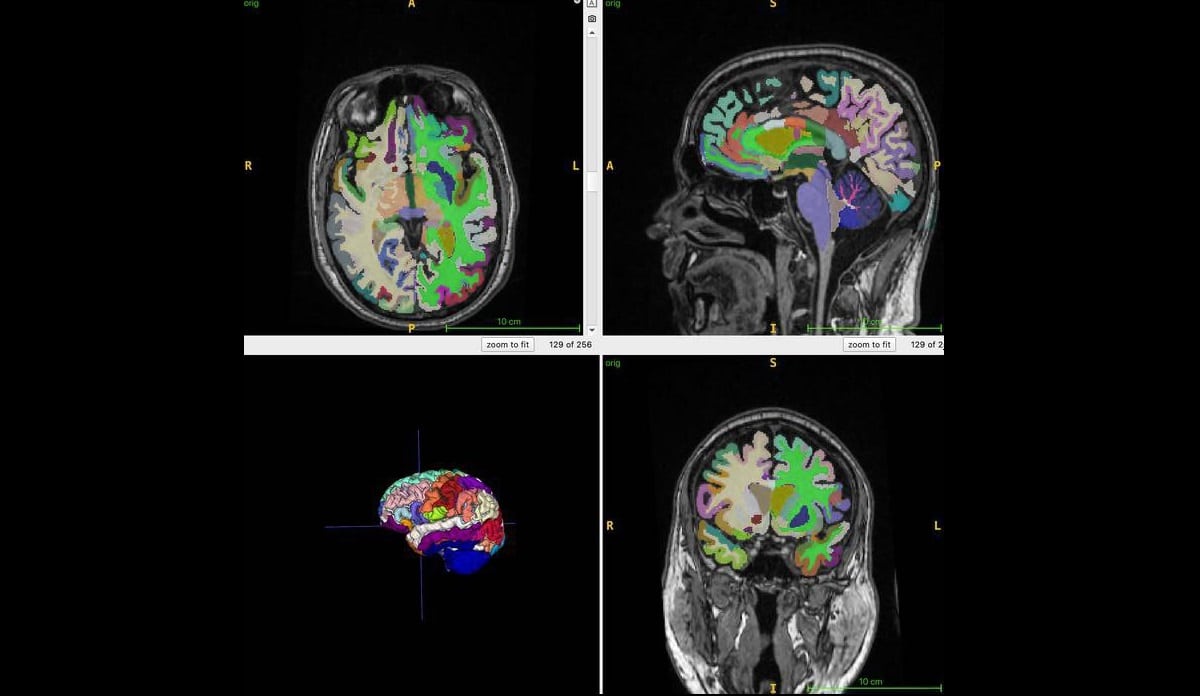

Во время исследования, которое сейчас еще продолжается, ученые обследовали с помощью МРТ тела 1164 здоровых человек из четырех клиник. Женщин среди них было 52%. Средний возраст участников — 55,17 года. Ученые использовали Т1-взвешенные последовательности. При использовании этого метода, жир на МРТ-снимках выглядит светлым, а жидкость — темной. Это помогает оптимально визуализировать мышечную, жировую и мозговую ткани. Алгоритм искусственного интеллекта авторы использовали, чтобы количественно оценить общий нормализованный объем мышц, висцерального жира на животе, подкожного жира и возраста мозга.

Исследователи обнаружили, что более высокое соотношение висцерального жира на животе к мышечной массе связано с большим возрастом мозга. Подкожный жир заметного влияния не оказывал.